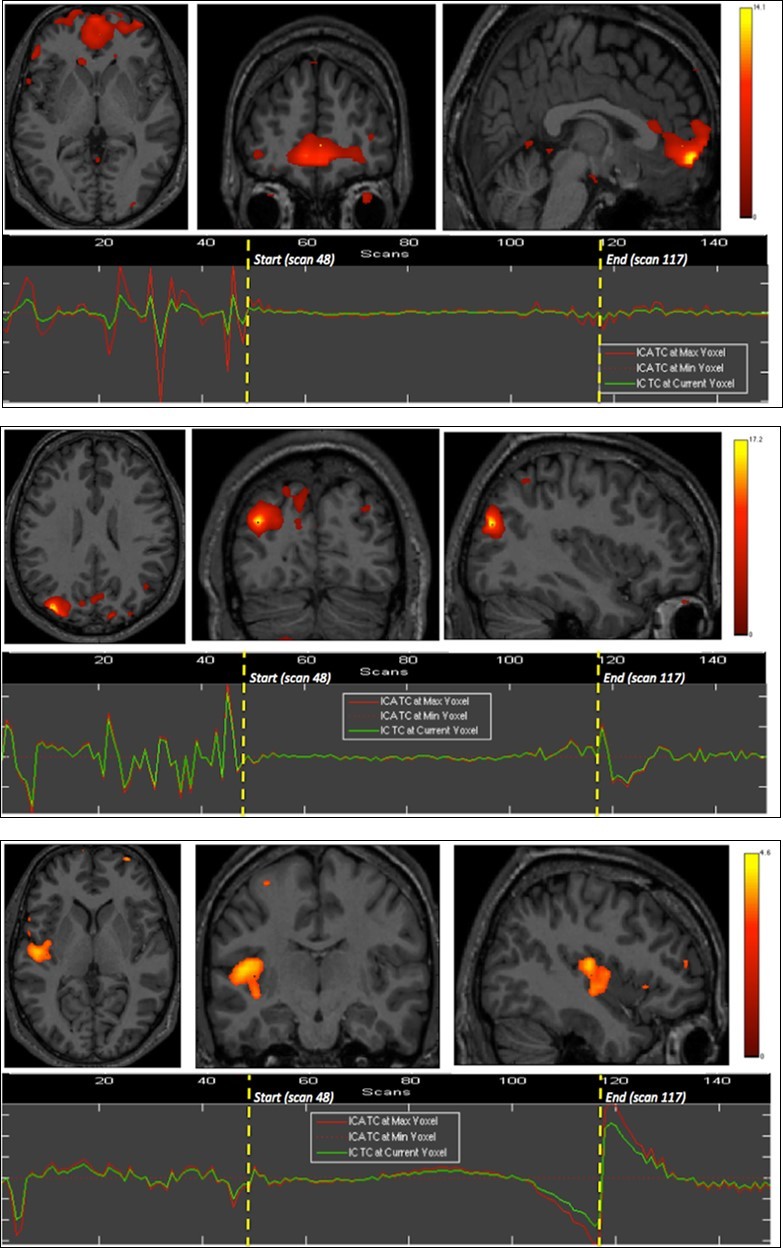

Right insula, bilateral orbitofrontal and right inferior parietal cortices were eloquent during the second breath holding (Figure 2).

Figure 2.Second experiment showing BOLD time courses and activation of ventromedial prefrontal cortex (upper row) and inferior parietal cortex including the angular gyrus (middle row) and the supramarginal gyrus (lower row).

The apnea period was obviously recognizable on the time course of the BOLD signals graphs because of the striking change of the curves from breathing to apnea and after apnea, with very low fluctuations during apnea. Within eloquent brain areas TC curves showed various patterns: (i) high fluctuations mainly in the second half of apnea in the dorsal pons only (Figure 1-1st row), (ii) very low fluctuations with deep depression at the end of apnea in the cerebellum (Figure 1-2nd row) as well as in the supramarginal gyrus (Figure 2, lower row), less marked in occipital areas (figure 1-4th row), and (iii) flat curve in dorsomedial prefrontal (Figure 1-3), ventromedial prefrontal (Figure 2-upper row) and inferior parietal areas (Figure 2-middle row). The eloquent areas disclosed during both experiments are mapped on a brain mesh as nodes of both networks (Figure 3).